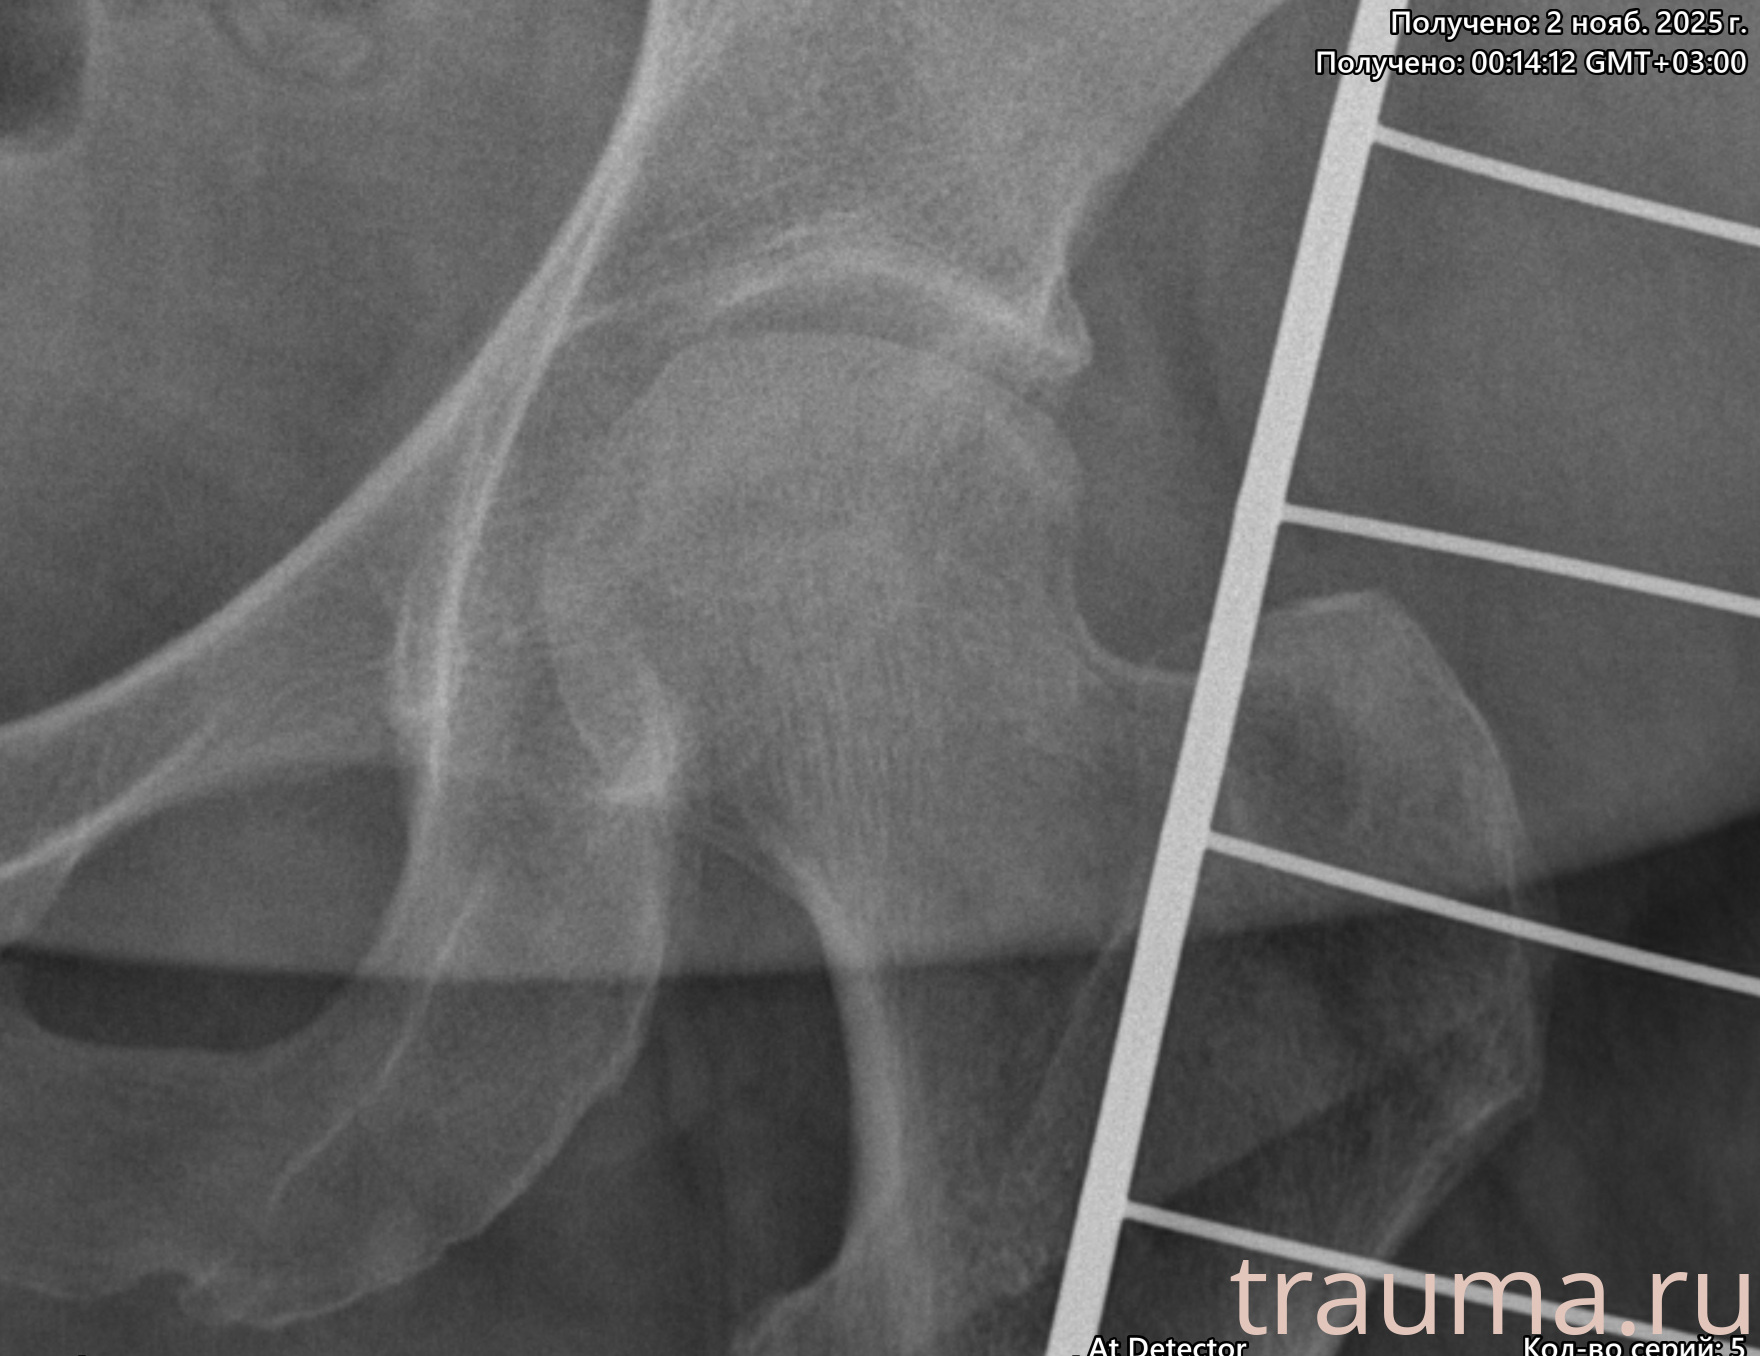

Рентген на дому: по вашему адресу приезжает врач-рентгенолог, травматолог-ортопед с мобильным рентгеновским аппаратом, проводит диагностику травмы или заболевания, делает необходимые рентгенограммы, дает рекомендации по дальнейшему лечению. Получить качественные снимки в домашних условиях возможно благодаря уникальной методике, разработанной МосРентген Центром для института  Склифосовского